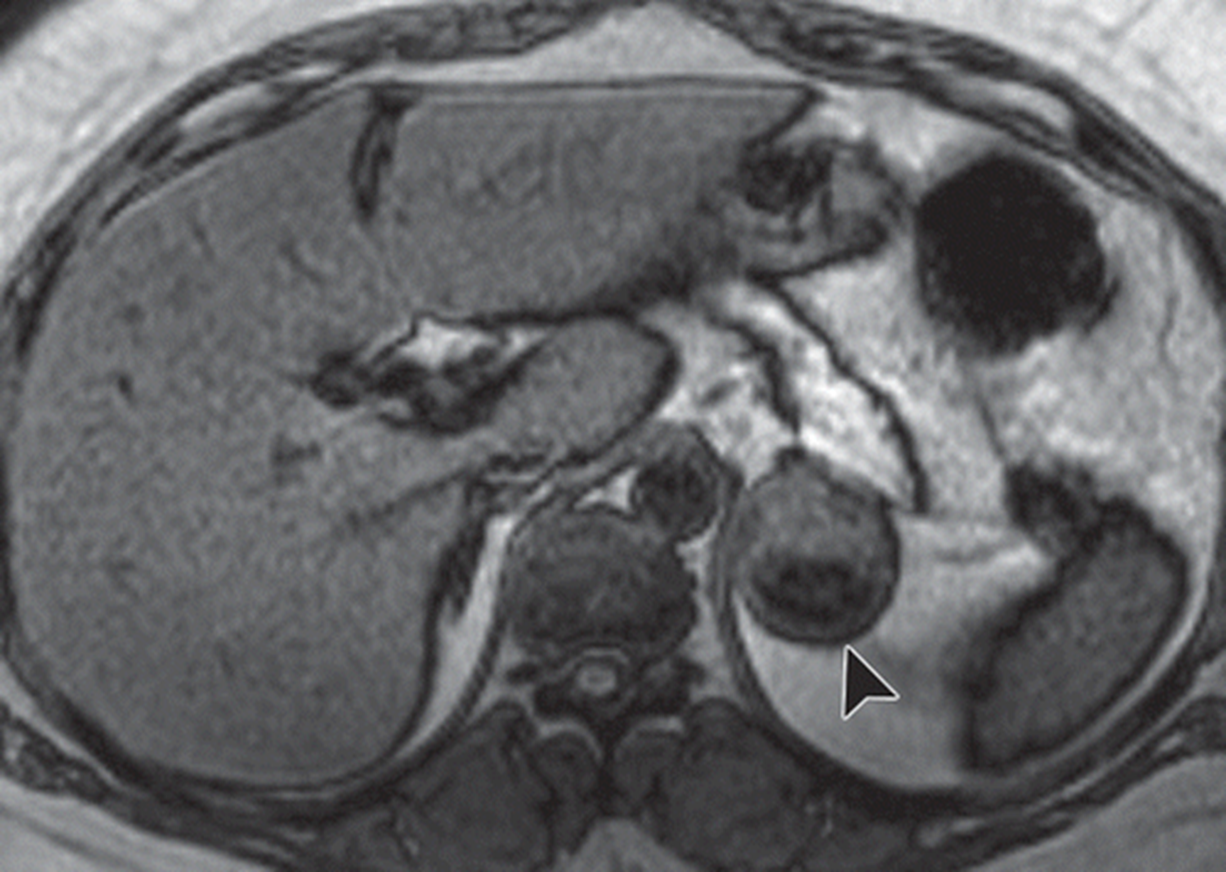

Nonfunctional Incidentalomas are often round and well circumscribed with heterogenous enhancement on imaging

You treat them based on their size and imaging characteristics

1) Small (less than 3 cm) you observe

2) > 4 cm you should surgically resect due to risk of adrenocortical carcinoma

3) in between 3-4 cm you should surveillance with imaging and labs

→ you can resect if good candidate